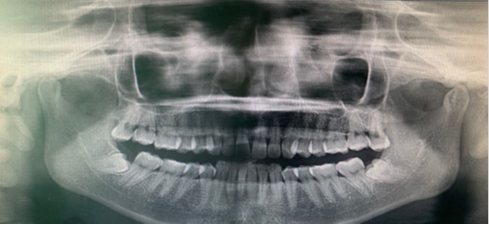

目前我科已正常开展全部治疗项目,口腔颌面外科门诊的常见疾病及治疗包括:简单的牙拔除术,复杂阻生牙(智齿)拔除术,根尖囊肿摘除术,牙槽骨突修整术,唇舌系带修整术,颌面部小肿物摘除术,唾液腺疾病,颌面部创伤,颌面部感染(牙源性及非牙源性),颌面部感染等。